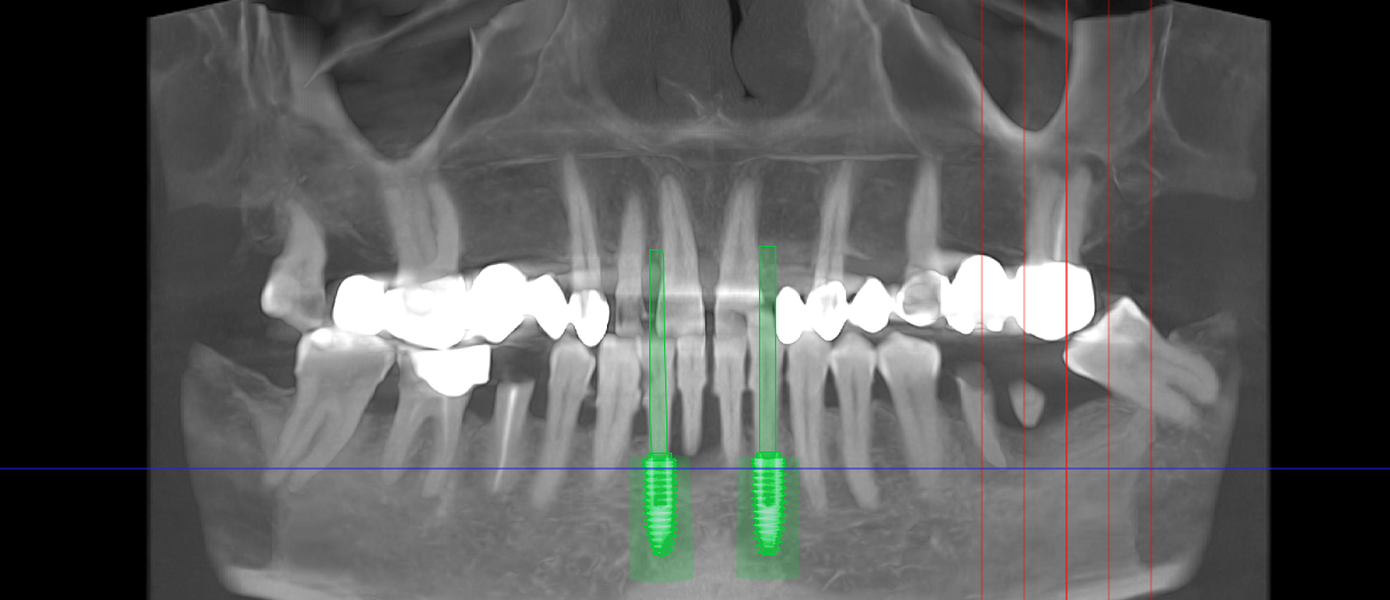

- Punte pe implanturi dentare – fixată pe 2 sau mai multe implanturi

- Șlefuirea dinților de susținere sau inserarea implanturilor

- Ai deja implanturi inserate și ai nevoie de restaurare protetică